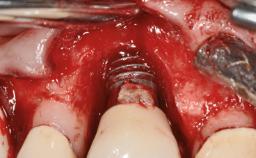

A male patient had lost teeth 11 and 22 as a result of a bicycle accident at age 14. In his adolescent years, a removable prosthesis had replaced the missing teeth. At age 21, the patient was referred by his dentist to the university clinic for treatment of the missing teeth 11 and 22 with implants. He was in good health and a nonsmoker. The absence of teeth 11 and 22 over many years had led to significant atrophy of the alveolar ridge, particularly at site 11. As a first step, the alveolar ridge was augmented using a block graft to replace the lost bone. A Straumann SP implant (diameter 4.1 mm, length 12 mm; Institut Straumann AG, Basel, Switzerland) and a Straumann Narrow Neck implant (length 10 mm) were inserted in the correct location and axial position at sites 11 and 22, respectively, six months later. After three months of healing and subsequent reentry, the patient returned to the referring dentist to receive the prosthetic restoration. The patient was seen again six months after the restoration had been placed. The frontal view showed a high smile line, an irregular gingival profile, and a bluish-gray tinge to implant crowns 11 and 22 compared to the natural dentition.